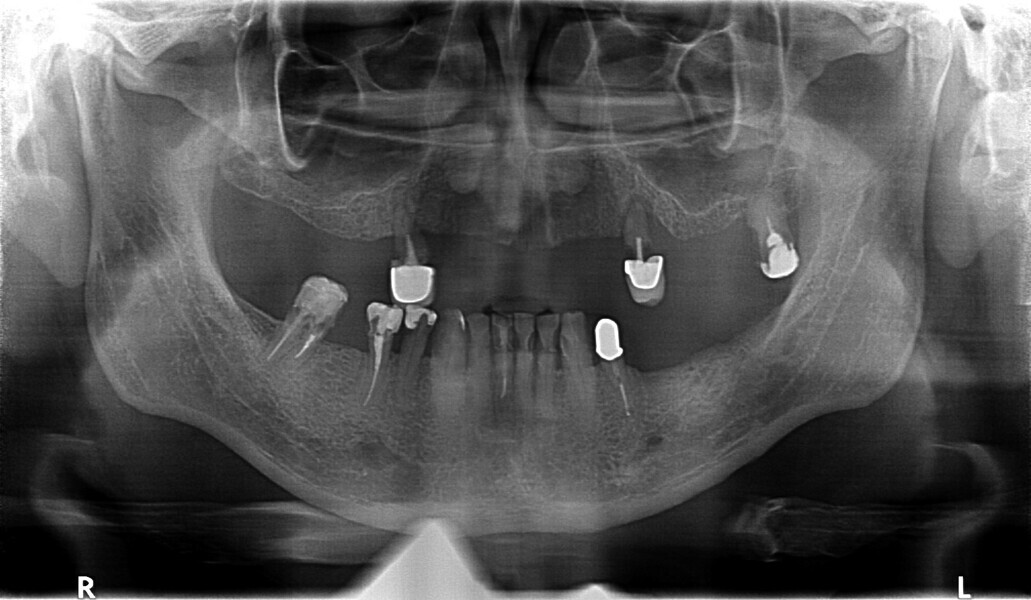

Fig. 29: OPG prior to treatment.